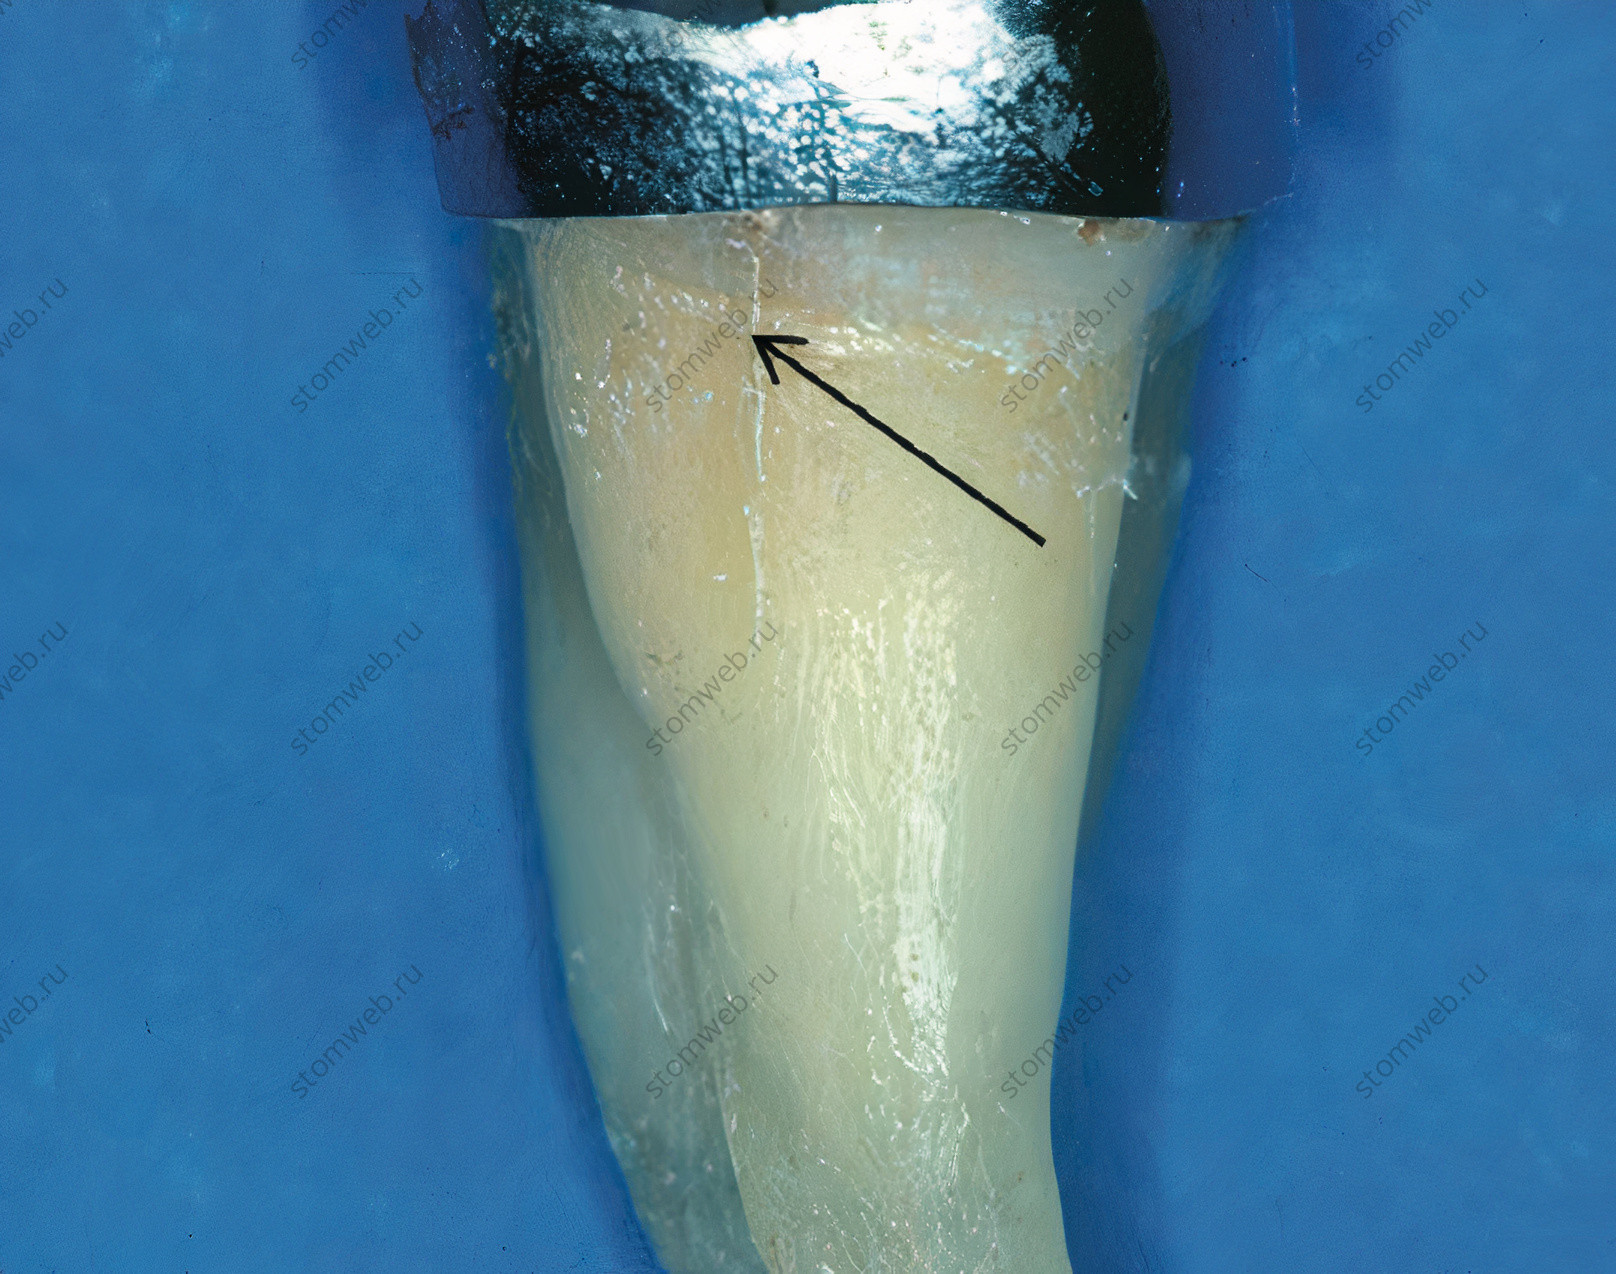

Переломы коронок появляются спонтанно и их этиологию трудно установить. Трещины обычно начинаются в коронковой части зуба и прогрессируют в апикальном направлении (Рис. 1). Эта категория будет позже описана более подробно.

Рисунок 1. Стандартный вид коронковой трещины на удаленном зубе (указано стрелкой). Эти трещины появляются в коронке и распространяются к апексу.